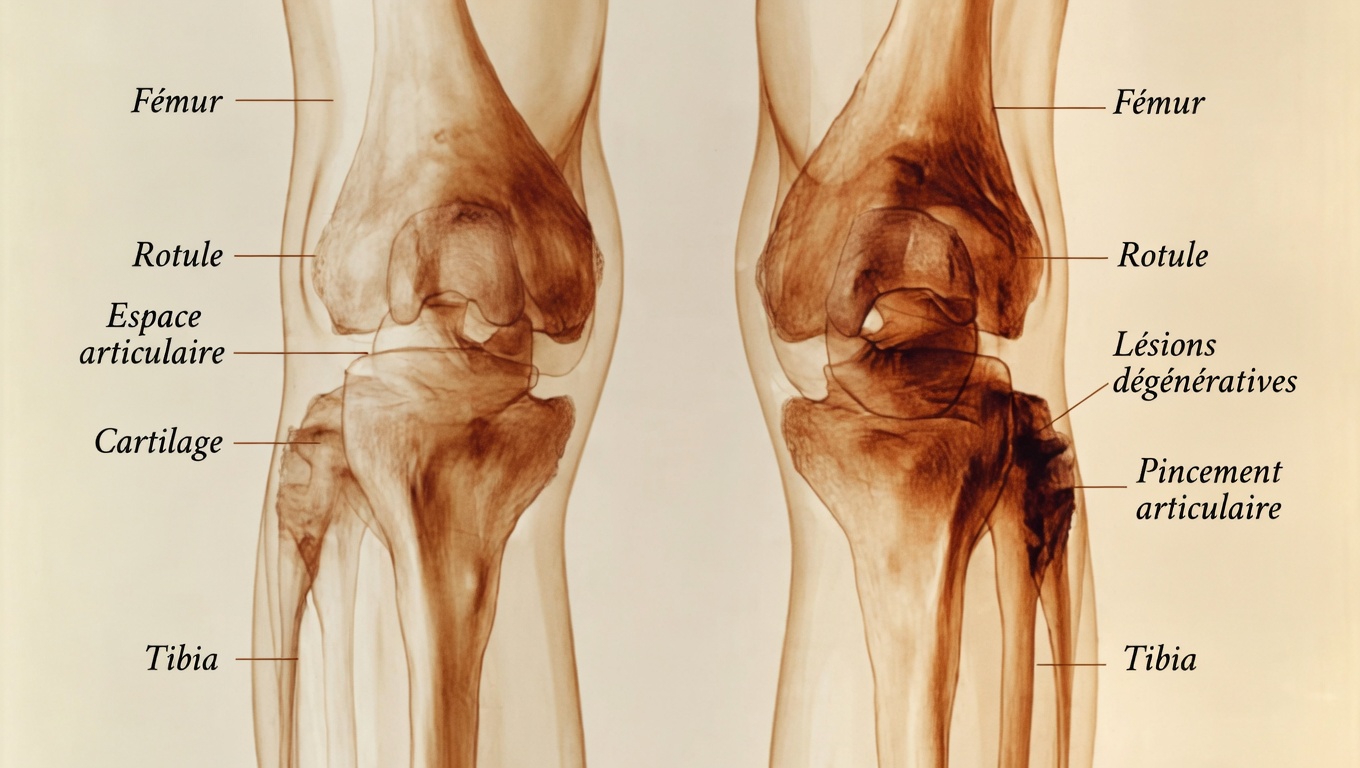

Mais son action ne s’arrête pas là. Les muscles dépendent également de la vitamine D pour mieux réguler leurs contractions et moduler certaines réponses inflammatoires du quotidien. Quand les niveaux sont insuffisants, l’organisme peut réagir par cette douleur diffuse bien connue, souvent localisée dans les genoux, les tibias ou les chevilles. Plusieurs travaux, notamment relayés par des institutions reconnues comme la Cleveland Clinic et Yale Medicine, soulignent l’importance de ce nutriment pour le confort physique de tous les jours autant que pour la santé du squelette.